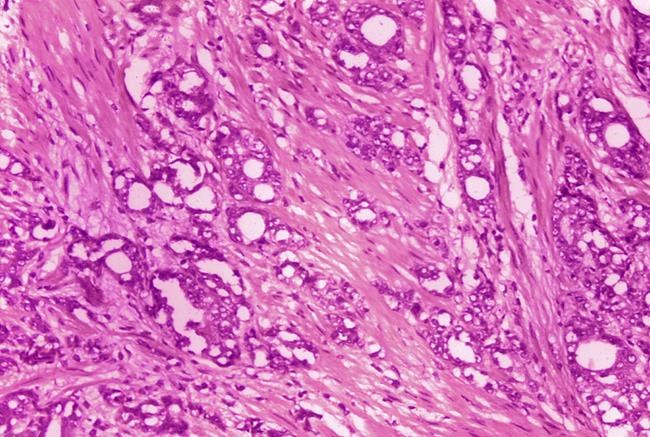

When a patient has a suspicious test result, a doctor might recommend a biopsy, which involves taking samples of tissue from the prostate gland. Next, a pathologist looks under a microscope and scores the samples for how abnormal the cells look.

Often, doctors offer patients with the lowest score — Gleason 6 — a way to avoid surgery and radiation: active surveillance, which involves close monitoring but no immediate treatment.